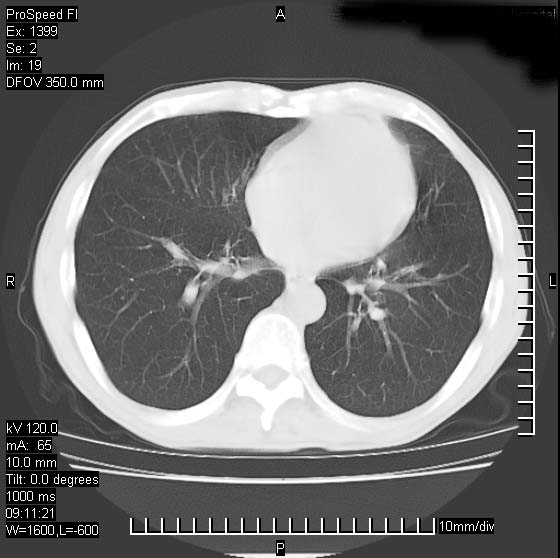

以下是引用卜一在2007-1-19 9:55:00的发言:[br]左肺沿胸膜下巨大肿块影,边缘呈分叶征,纵隔内见肿大淋巴结,右肺内另见一不规则结节影 .考虑:左肺周围性肺癌伴纵隔 右肺内转移.

以下是引用rgsyyf在2007-1-19 11:05:00的发言:[br]左肺上叶见形态不规则巨大软组织肿块影,边缘呈分叶征,纵隔内隆突下见肿大淋巴结,右肺内另见一不规则结节影 .考虑:左肺周围性肺癌伴纵隔即右肺内转移.